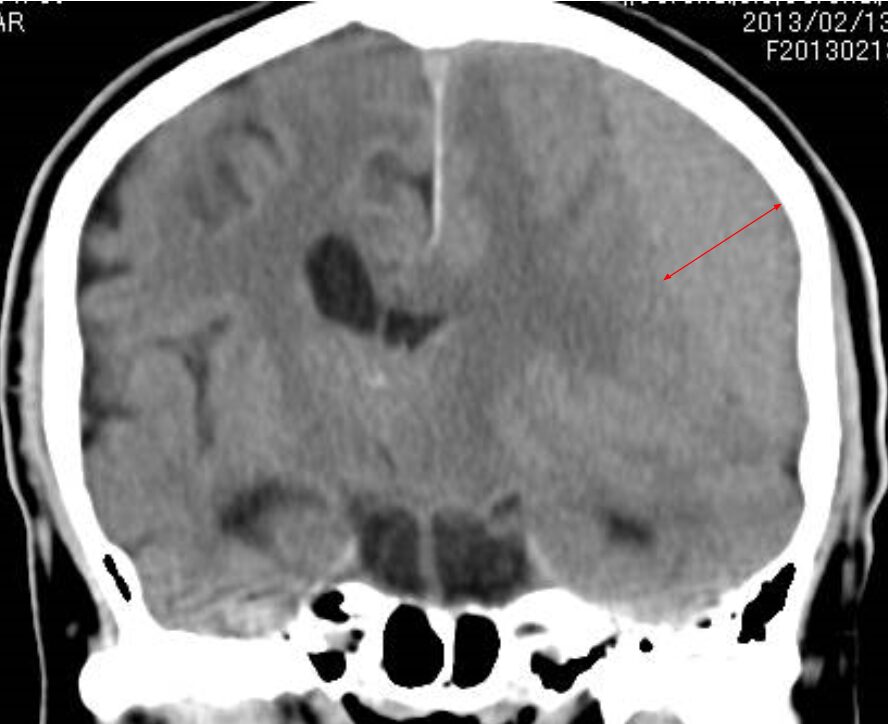

慢性硬膜下血腫

頭部を強くぶつけたり、転倒した際に病院で頭部検査異常なしと診断されても、2週間~3ヶ月程度時間が経過したのち頭蓋内に血が溜まることがあります。具体的には頭痛や体半分の麻痺(左右どちらかはわかりませんが、突然強い麻痺が出現する脳梗塞などとは違い、軽度の麻痺が徐々に進行することで発症)や意識障害などで発症します。

この疾患は若年者には発症しません。70歳以上の高齢者の方に多く発症します。40歳以降の中年期でも頭部外傷後、しばらく経過して強い頭痛を感じたりする際は慢性硬膜下血腫を発症していることもあります。頭部外傷後の頭痛や体が思うように動かせないなどの症状がある際は、必ず頭部検査を受けるようにしてください。